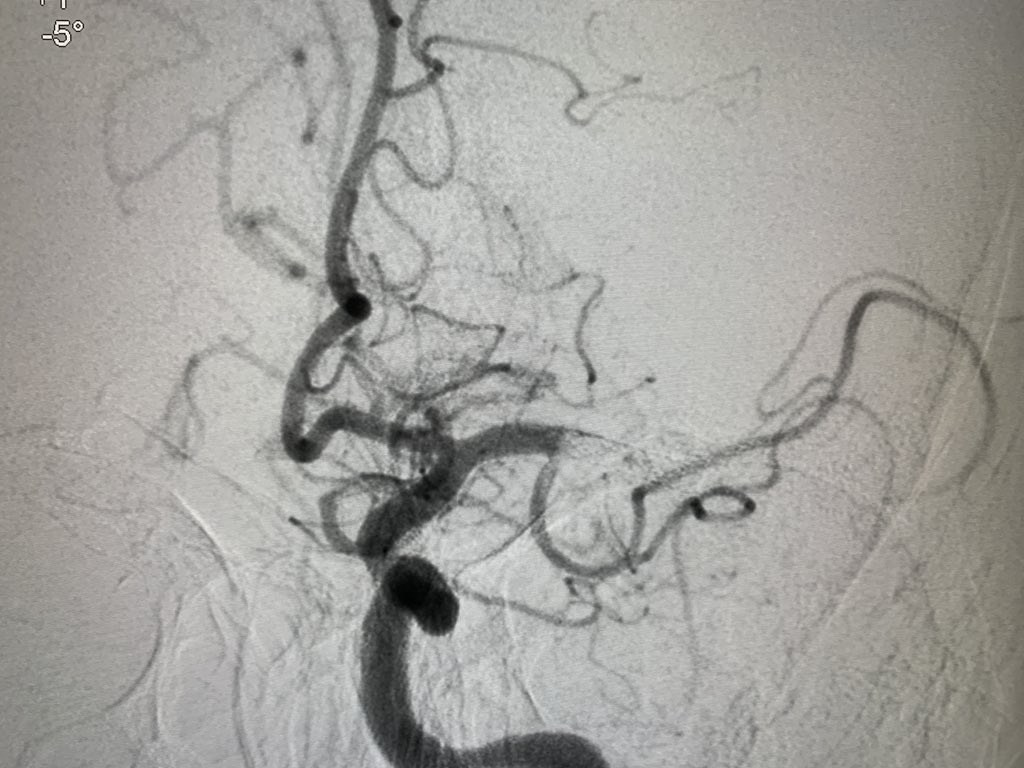

Tight stenosis opened up with a Balloon mounted stent and final result